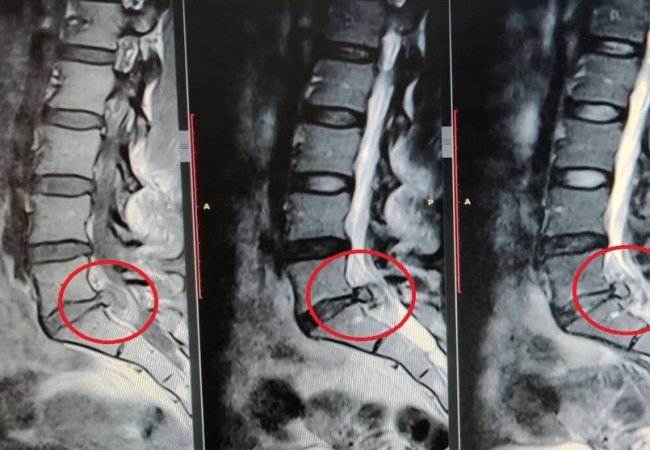

У Ковельському МТМО лікарі видалили чоловіку міжхребцеву грижу, розміром 14 мм, яка загрожувала втраті функцій нижньої кінцівки.

Після проведення магнітно-резонансної томографії поперекового відділу хребта медики виявили грижу міжхребцевого диску розміром 14 мм. Такий діагноз був прямим показом до термінової операції, адже є загроза втрати функцій кінцівки.